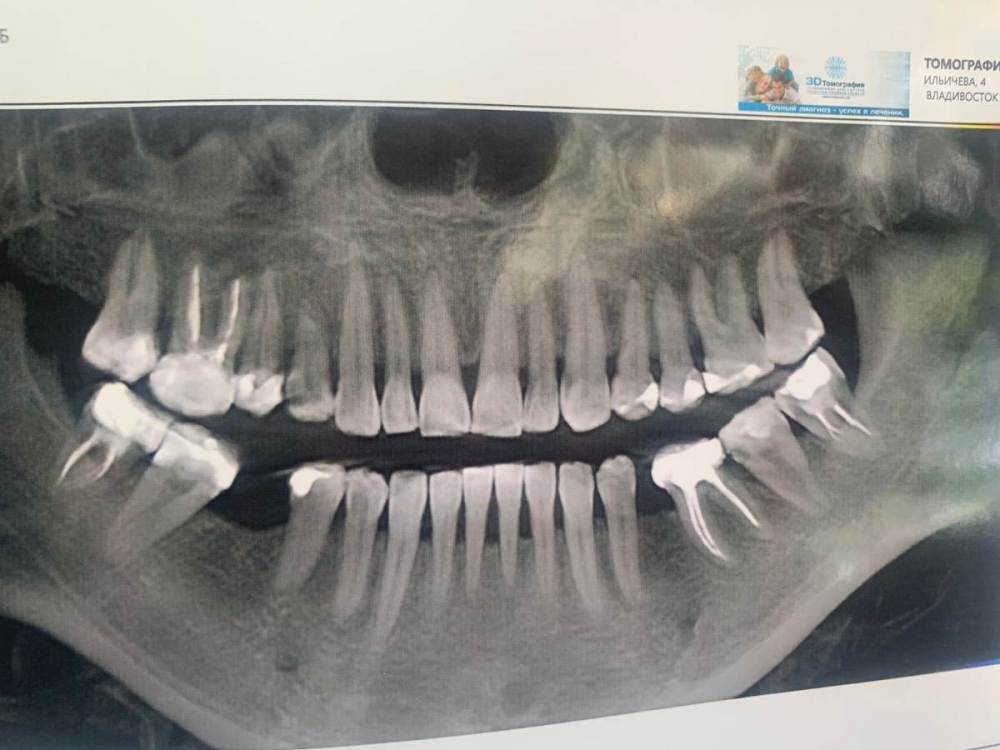

Ankauragan Опубликовано 12 декабря, 2023 Поделиться Опубликовано 12 декабря, 2023 Над 6 ой верх слева (на фото справа) - стал появляться исчезать 2 раза в этом месяце свищ, на снимке видно разрежение, можно ли вылечить или удаление?? Ссылка на комментарий

DoctorT Опубликовано 13 декабря, 2023 Поделиться Опубликовано 13 декабря, 2023 48 минут назад, Ankauragan сказал: Это я тоже прочла) про отток , Можно не удалять зуб? Видно по снимку разряжение это фатальное или попробовать лечить? мой совет - удалять. Состояние самого зуба (изменен в цвете , на 90% выполнен пломбой, разряжение в области расхождения корней, скорее всего есть подвижность) весьма плачевное. 2 Ссылка на комментарий